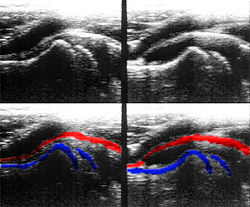

Bei der farbkodierten Doppler-Sonografie wird für einen großen Bereich eines konventionellen Ultraschallbildes (Color-Window) die örtliche Doppler-Frequenz (= mittlere Flussgeschwindigkeit) und deren Schwankungsbreite bestimmt. Damit möchte man die Turbulenz der Strömung abschätzen. Aufgrund der statistischen Bewegungen der Streuteilchen ist die Schwankungsbreite der Fließgeschwindigkeit jedoch stets größer als die Turbulenz. Das Ergebnis wird in Falschfarben auf dem B-Bild überlagert, also in Farbtönen von rot und blau für verschiedene Blutgeschwindigkeit und grün für Turbulenz. Hierbei steht üblicherweise die Farbe Rot für Bewegung auf den Schallkopf zu, während mit blauen Farbtönen Flüsse weg von der Sonde codiert werden. Bereiche der Geschwindigkeit 0 werden durch die Elektronik unterdrückt.

Farb-Doppler und PW-Doppler. Innerhalb der Stenose ist wegen der hohen Flussgeschwindigkeit und des resultierenden Alias-Effekts die Geschwindigkeit in Blau kodiert. -